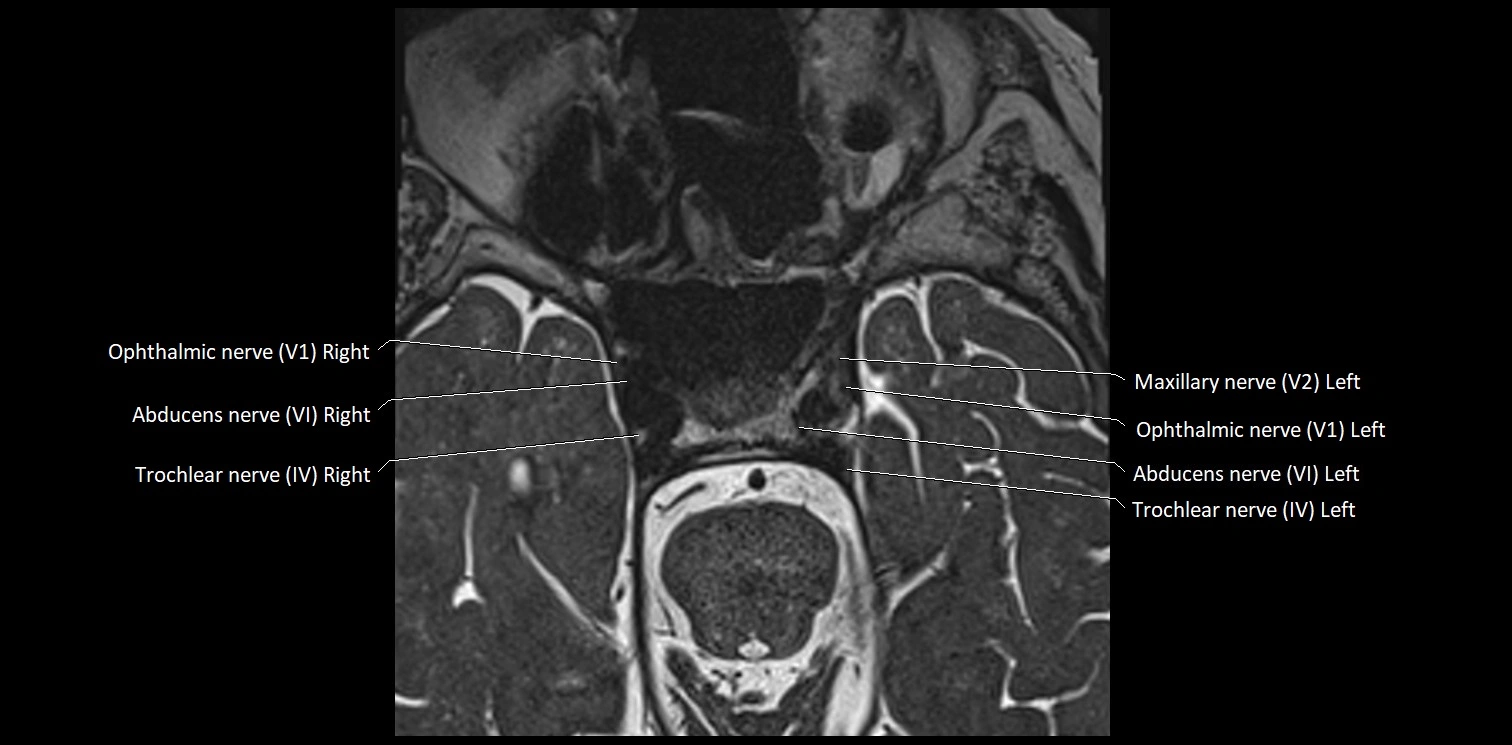

MRI Appearance

• The abducens nerve is a small, thin, linear structure

• Best visualized on high-resolution T2-weighted 3D MRI sequences (e.g., FIESTA or CISS)

• Seen as a hypointense (dark) line running from the brainstem at the pontomedullary junction, traversing the prepontine cistern, and entering Dorello’s canal under the petrosphenoidal ligament, then into the cavernous sinus, and finally the orbit

• May be challenging to visualize in standard MRI due to its small size

• Pathology may be inferred by absence, displacement, or enhancement of the nerve

MRI images

image